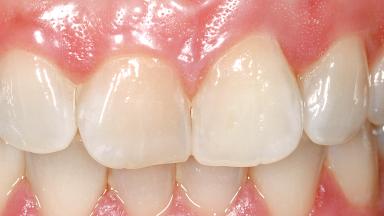

A 29-year-old female patient presented for treatment to replace the upper left central incisor tooth with an implant- supported restoration. The tooth had been intermittently symptomatic for the previous 12 months. The tooth had originally suffered trauma about 15 years previously. Several endodontic treatments had been performed, including an apicectomy procedure to retain the tooth. The patient was healthy and a non-smoker. She had reasonable expectations in regard to esthetic outcomes and the risk of marginal tissue recession following treatment. At medium smile, the gingival margins of the upper teeth were visible, with a display of 3 to 4 mm of the gingival margins. Gingival recession of tooth 21 and a discrepancy in the gingival levels between teeth 11 and 21 was observable during normal speech and smile.

Soft Tissue Anatomy Intact Defective

Bone Volume Horizontally and vertically sufficient Horizontally deficient Deficient vertically or deficient vertically AND horizontally